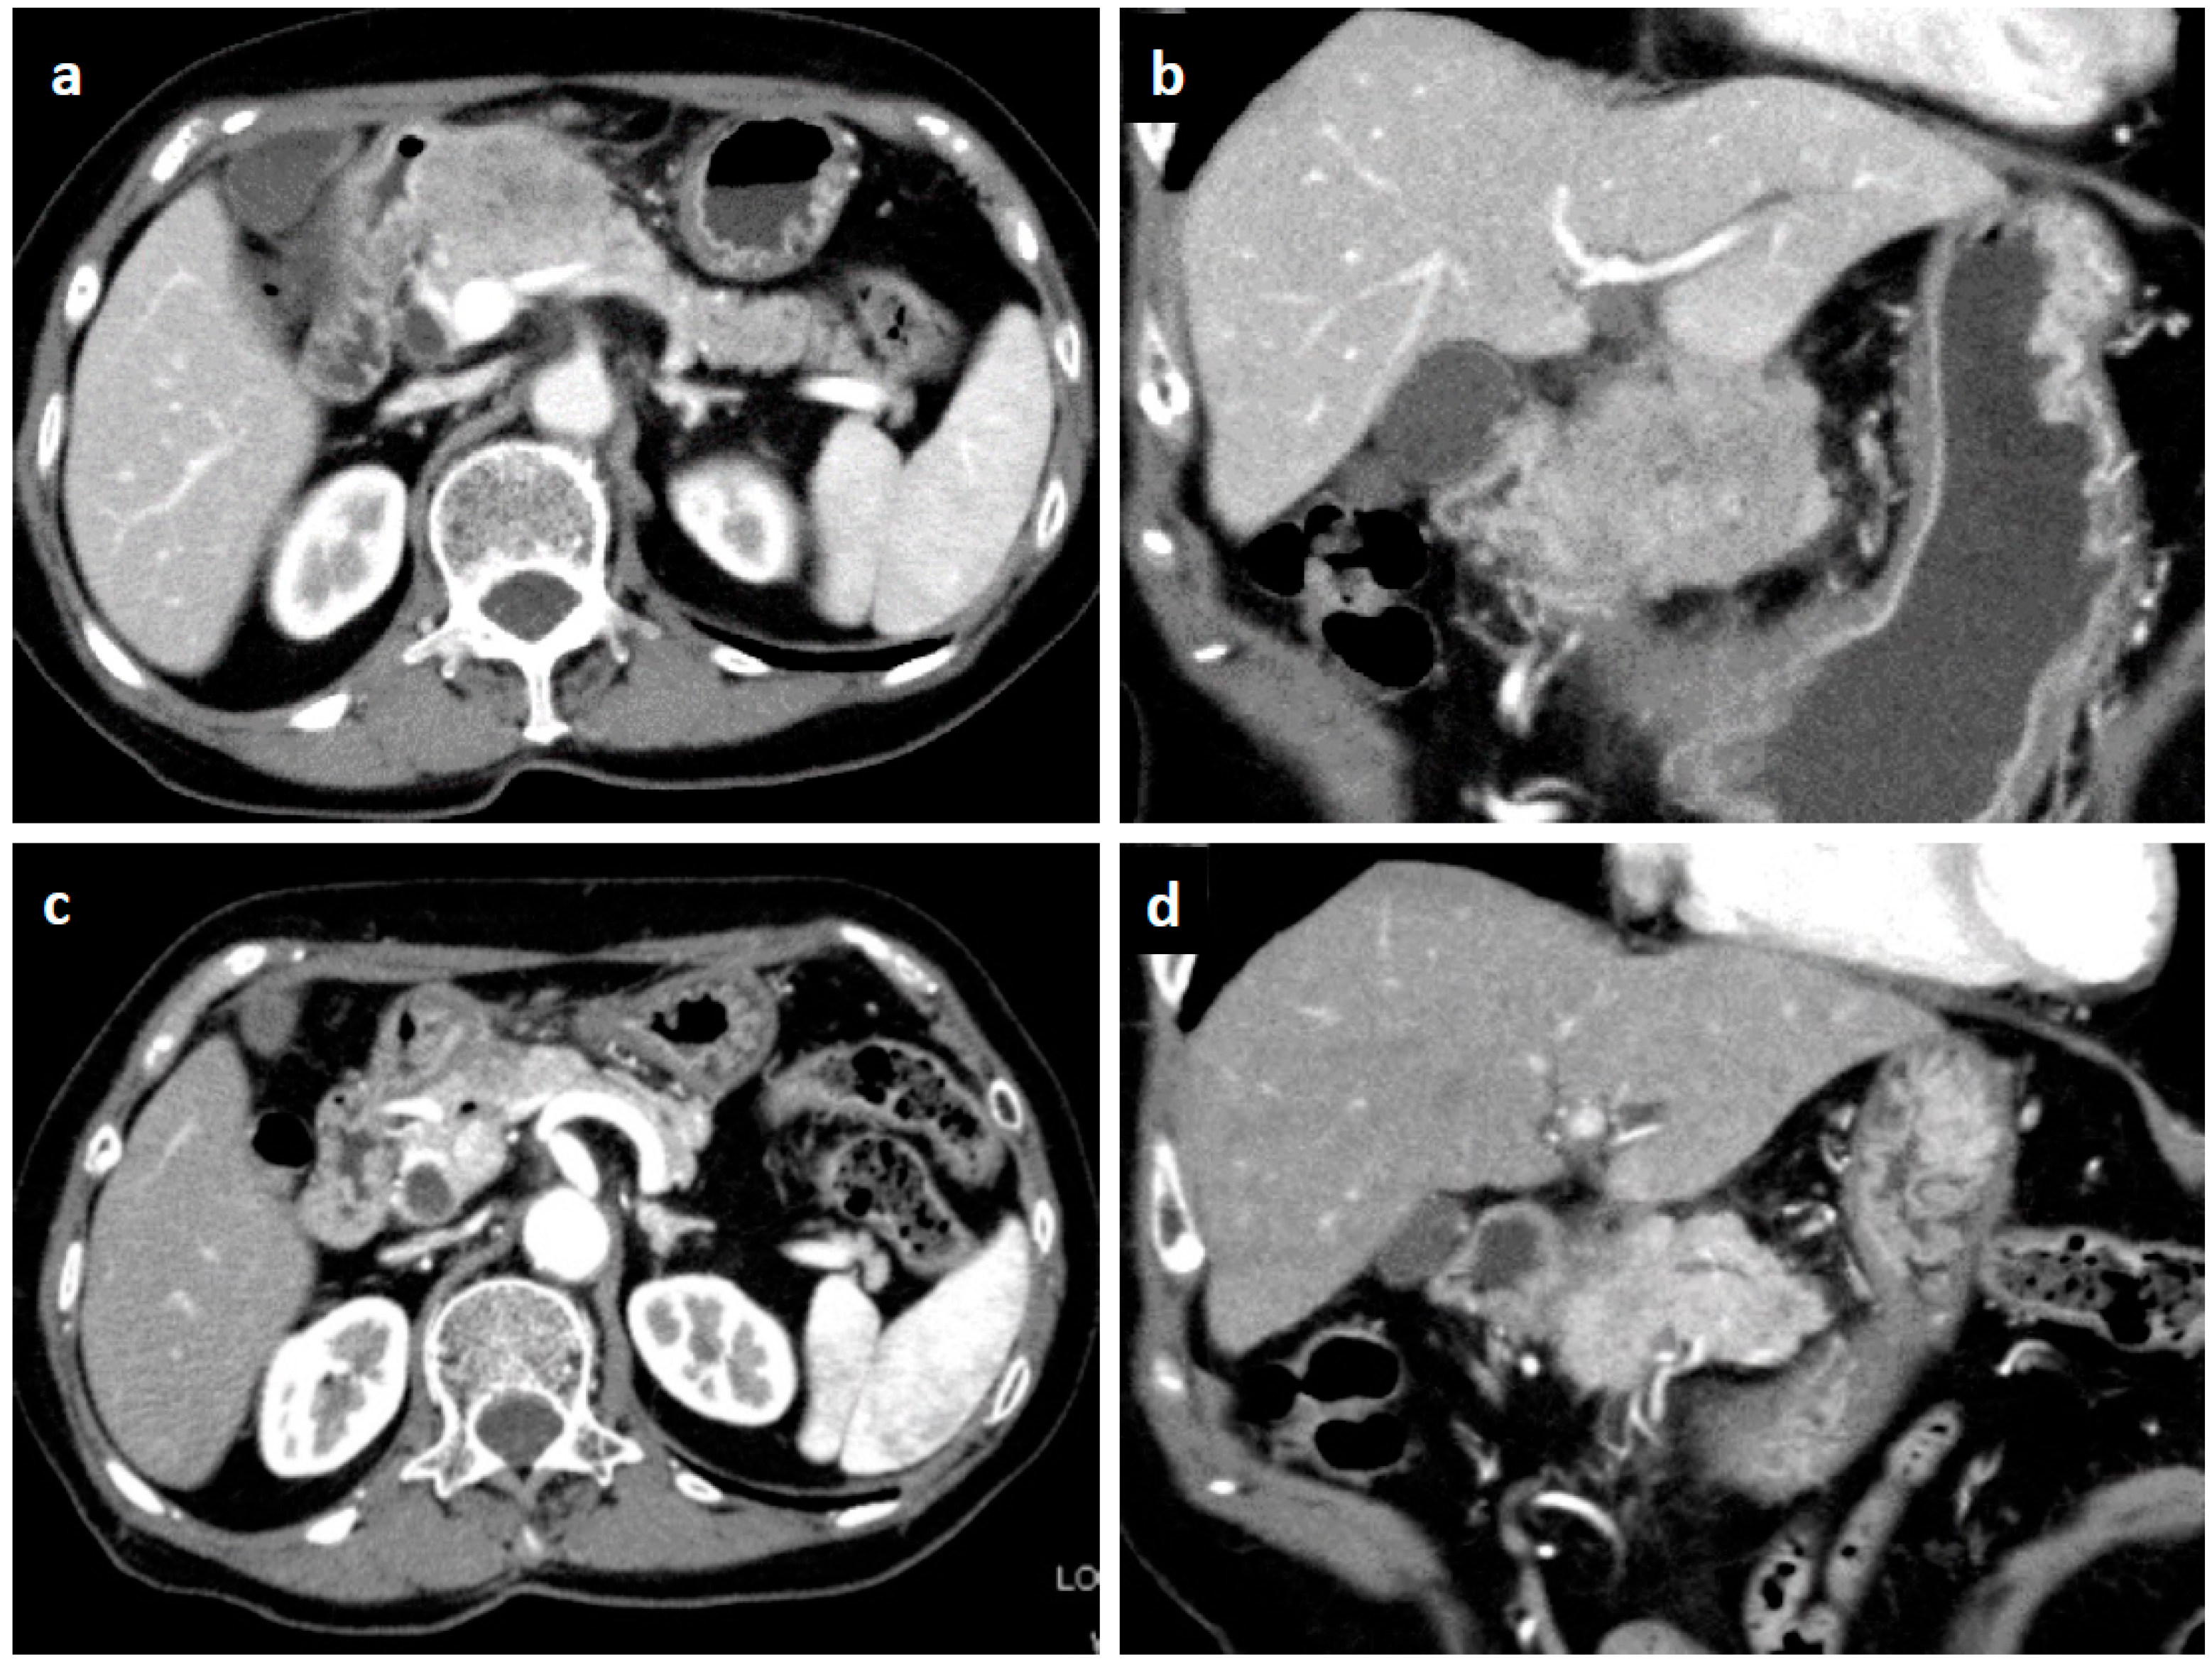

2. Case Presentation